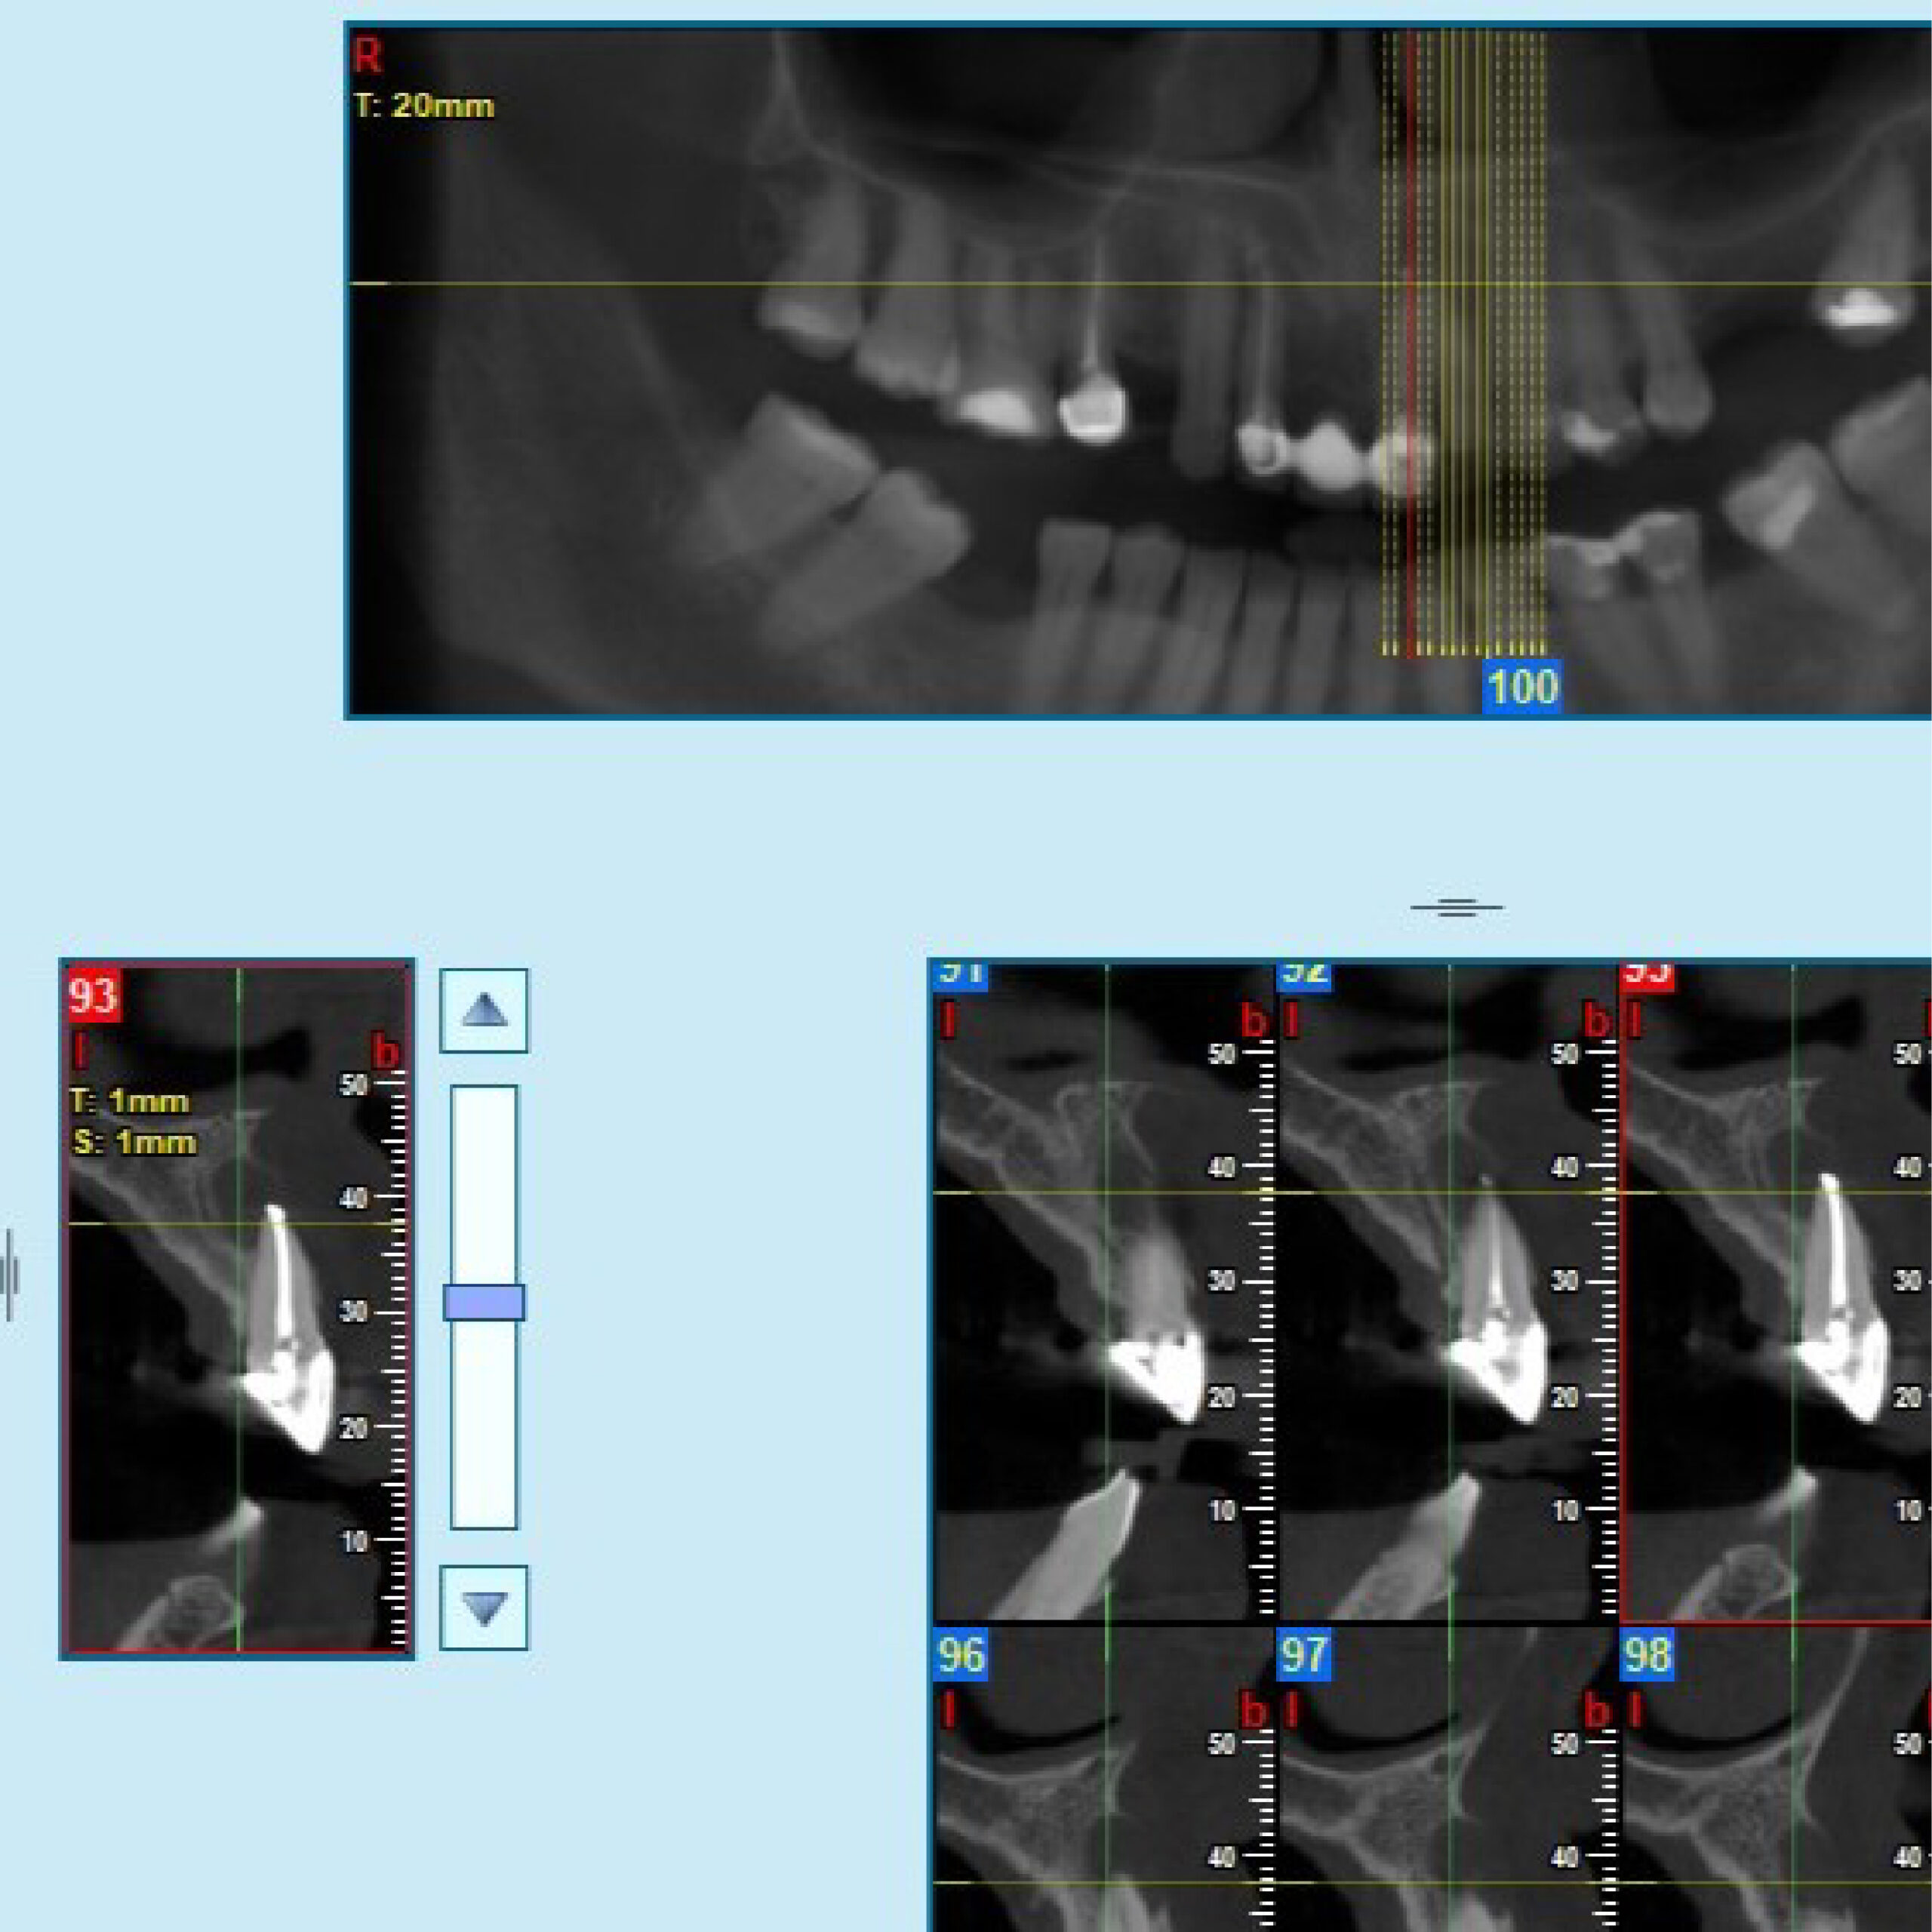

Radiografías

* Haz click sobre las radiografías para verlas a mayor tamaño